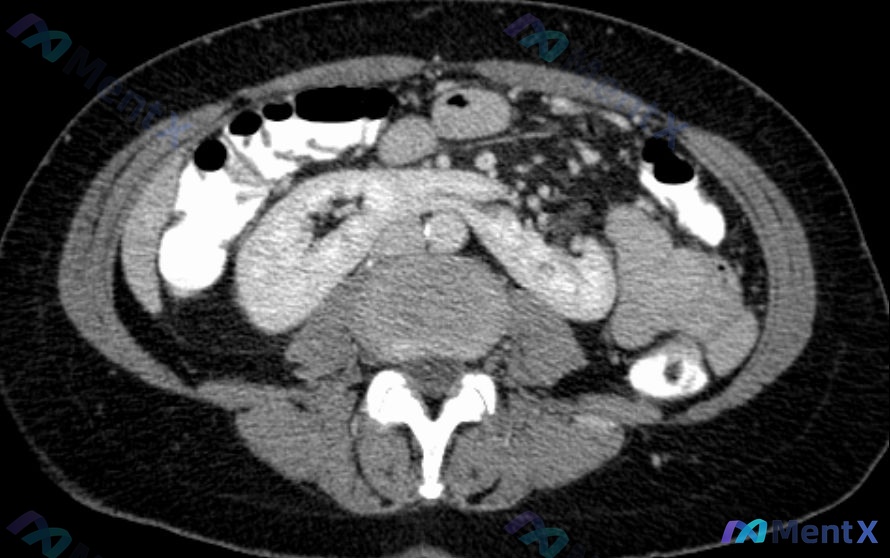

病例资料整理 患者信息:25 岁女性 主诉:复发性尿路感染评估 病史:过去一年 5 次膀胱炎,1 次肾盂肾炎。无其他已知健康状况。近 6 个月无性行为。 体征:T 37.7°C, P 84, R 17, BP 110/70。轻度耻骨上压痛。 影像检查:腹部和骨盆 CT 扫描(冠状位)。 影像所见 C...

病例资料 患者信息:11 岁女孩 主诉:脐周间歇性剧烈疼痛 1 天 既往史:无重要既往病史 现病史:近期有学校动物园旅行史。体格检查脐周轻度压痛,无反跳痛,肠鸣音正常。 初步诊断:肠系膜淋巴结炎(腹部影像支持) 意外发现 在腹部影像检查中,除了淋巴结肿大外,还有一个偶然的肾脏发现(见图/描述): -...